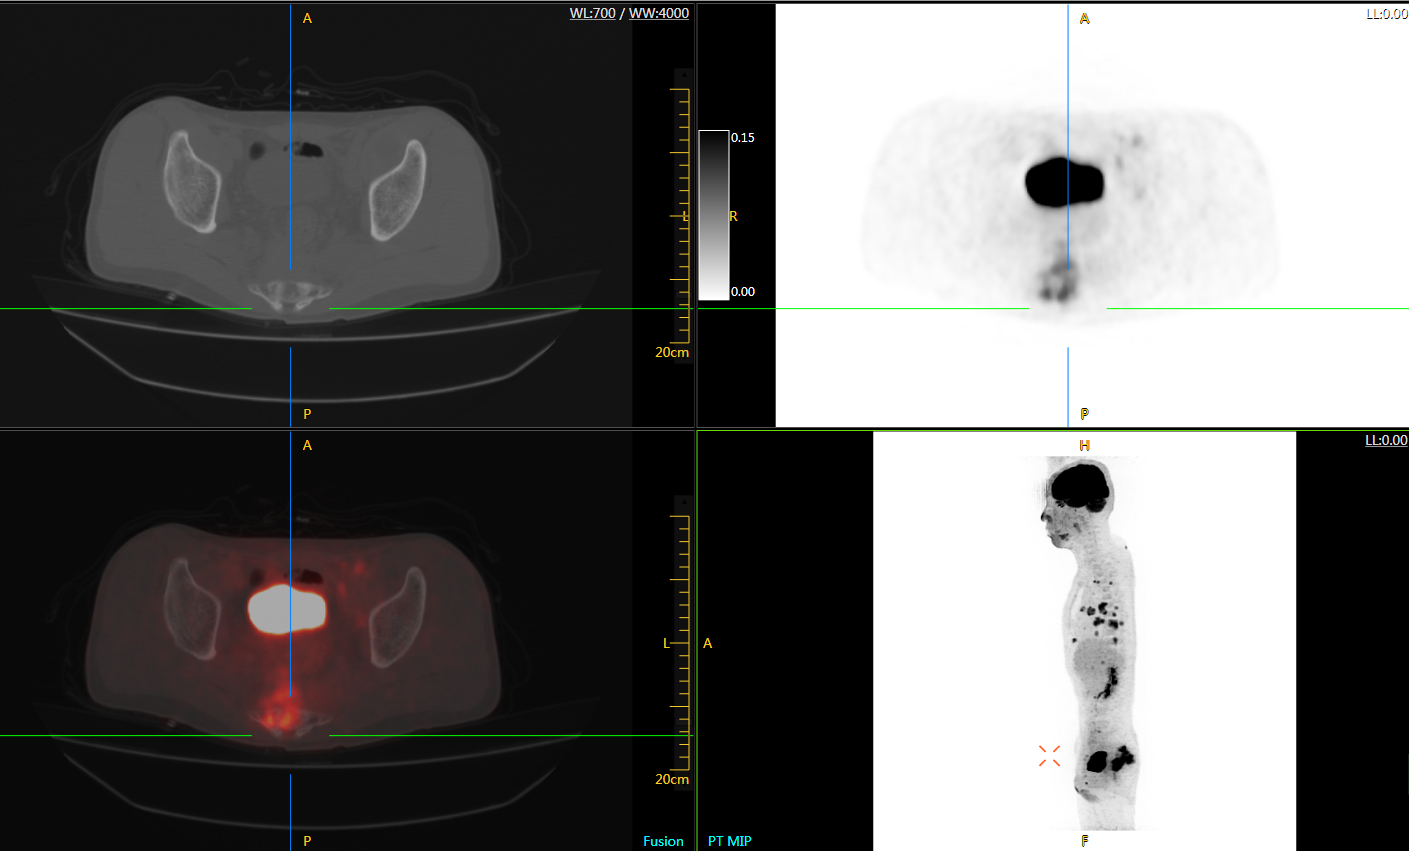

直腸癌

男,45歲,直腸癌術(shù)后9個(gè)月,發(fā)現(xiàn)肺占位

臨床診斷:直腸區(qū)術(shù)后改變,復(fù)發(fā)伴骶骨受累,雙肺多發(fā)轉(zhuǎn)移